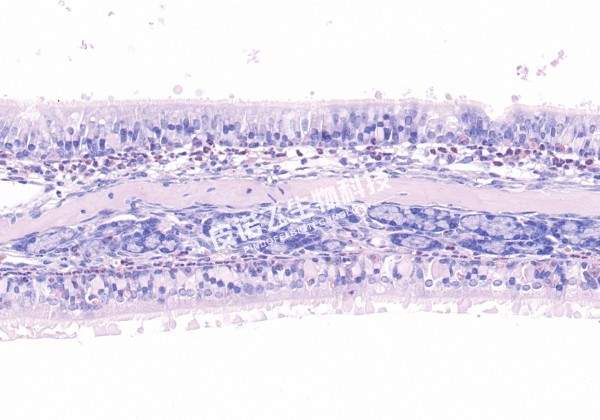

变色酸染色

变色酸染色 25一张